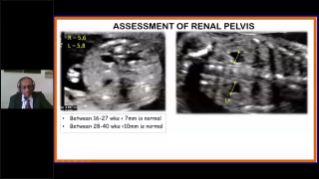

Supportata dalla piattaforma avanzata ZST+, la gamma completa di soluzioni smart di Nuewa ├© progettata appositamente per migliorare la salute della donna durante il periodo pre-gravidanza, la gravidanza e il recupero post-parto, per fornire diagnosi complete ed efficaci e per rispondere a sfide cliniche sempre pi├╣ impegnative.